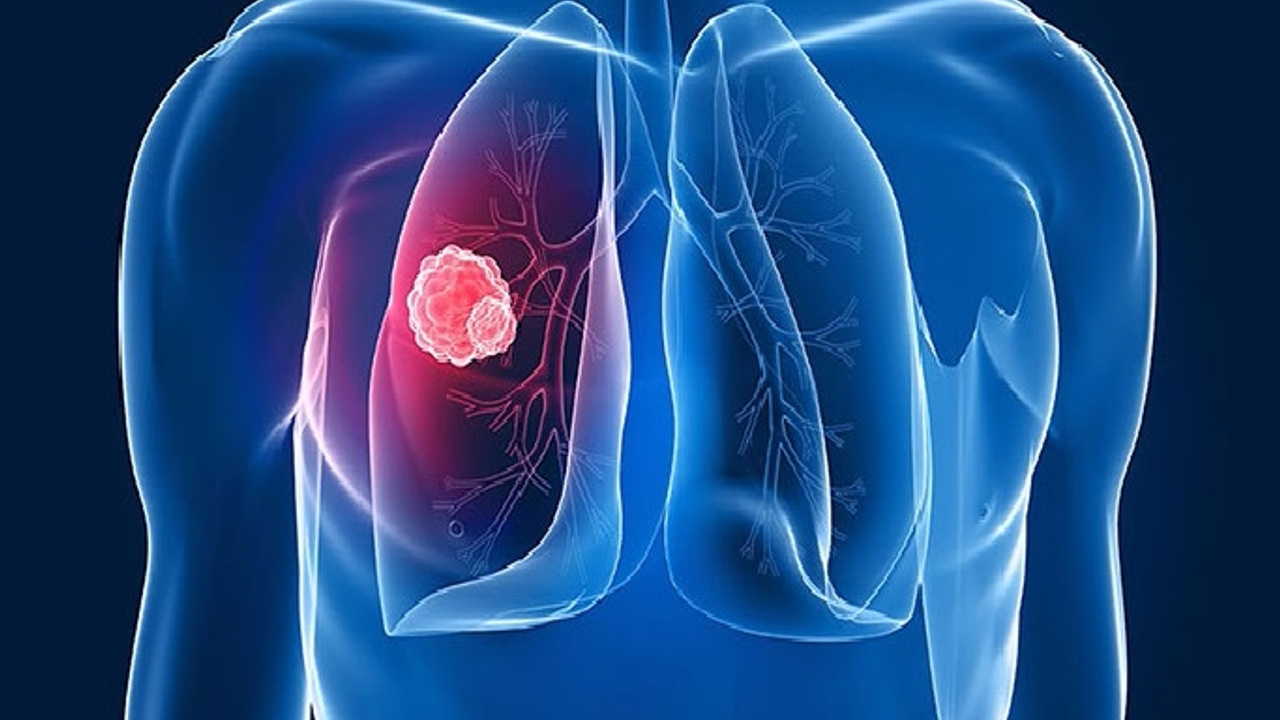

- Akciğer kanseri, dünya çapında yaygın kanser türlerinden biri olarak ön plana çıkıyor. Akciğer kanseri son yıllarda hem gelişmiş hem de gelişmekte olan ülkeler için önemli bir ölüm nedenidir. Tütün ve tütün ürünleri kullanmak akciğer kanserinin en büyük risk faktörlerinden biridir. Akciğer kanseri erken teşhisi için basit bir parmak testini yapabilirsiniz.

- Akciğer kanseri, dünyada en yaygın üçüncü kanserdir ve her geçen yıl hastalık daha yaygın hale geliyor. Her yıl yaklaşık 46.400 kişiye teşhis konuyor. Geçtiğimiz yılın Sağlık Bakanlığı verilerine göre, Türkiye’de yılda ortalama 23 bin erkeğe ve 4 bin 500 kadına akciğer kanseri teşhisi konuluyor.

- AKCİĞER KANSERİ NEDİR? Küçük hücreli olmayan akciğer kanseri (KHDAK) veya küçük hücreli akciğer kanseri (SCLC) olmak üzere iki ana Akciğer kanseri türü vardır. Bazen kanser vücudun başka bir yerinden akciğerlere yayılabilir. Buna akciğer metastazı veya ikincil akciğer kanseri denir. Akciğer kanserinin erken belirtilerini bilmek, riskinizi belirlemenize yardımcı olabilecek Schamroth pencere testi olarak bilinen evde yapılan bir parmak testi ile ortaya çıkabilir.